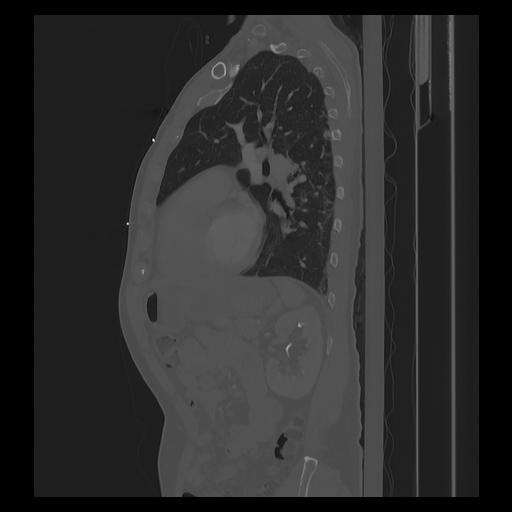

33 PULMON,CE,Sagittal,3.000,PULMON,Sagittal,